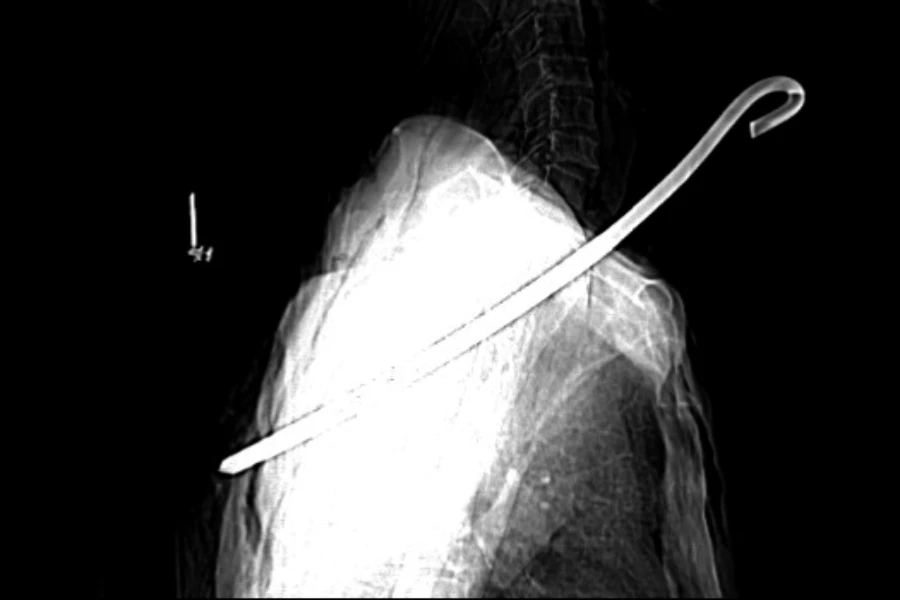

Hình ảnh chụp CT-Scan cho thấy cây sắt đâm thấu cổ ông Đ. |

Kết quả chụp CT-Scan cho thấy, dị vật kim loại đường kính 0,8 cm dài khoảng 30 cm xuyên từ vùng cổ phải qua phổi phải và trung thất xuống vùng ngực bên trái ông Đ. Cây sắt này cũng làm tổn thương rách thùy trên phổi phải, tràn khí màng phổi trái, tràn khí dưới da thành ngực và vùng cổ; gãy cung sau xương sườn số 5, 6 bên trái, gãy xương bả vai trái…